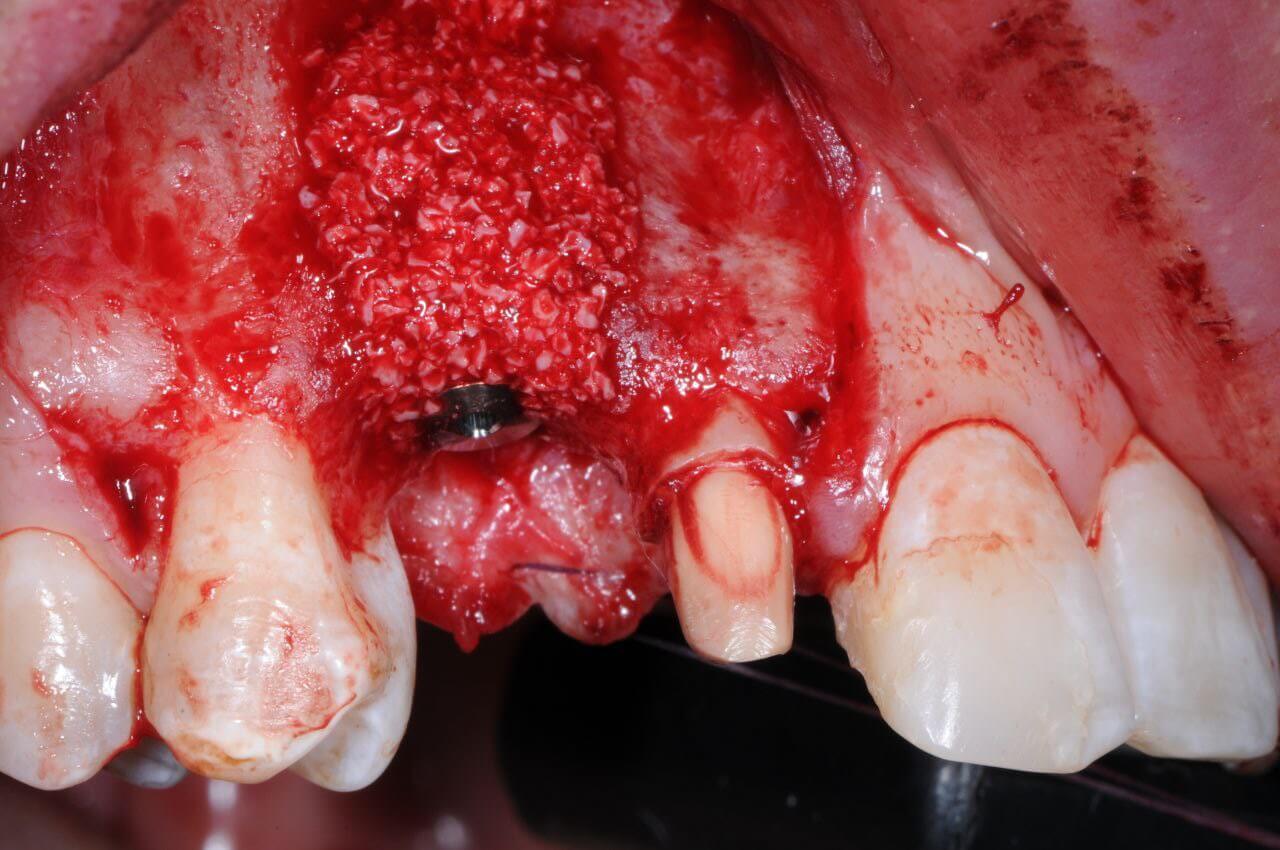

Артавазд Гагикович Зограбян

В данный момент представлено множество хирургических методик для восстановления дефекта слизистой оболочки, у клинициста часто возникает вопрос: «Какой метод выбрать?»

Также клиническая вариация дефекта многочисленна. У практикующего специалиста возникает «ступор»: какой дефект лечить вообще, какой дефект лечить в первую очередь, а какой оставить в связи с недостатком тканей нёба?

Мой доклад ответит на эти и другие вопросы.

Имплантация. Принципиальное значение костной и мягкой тканей